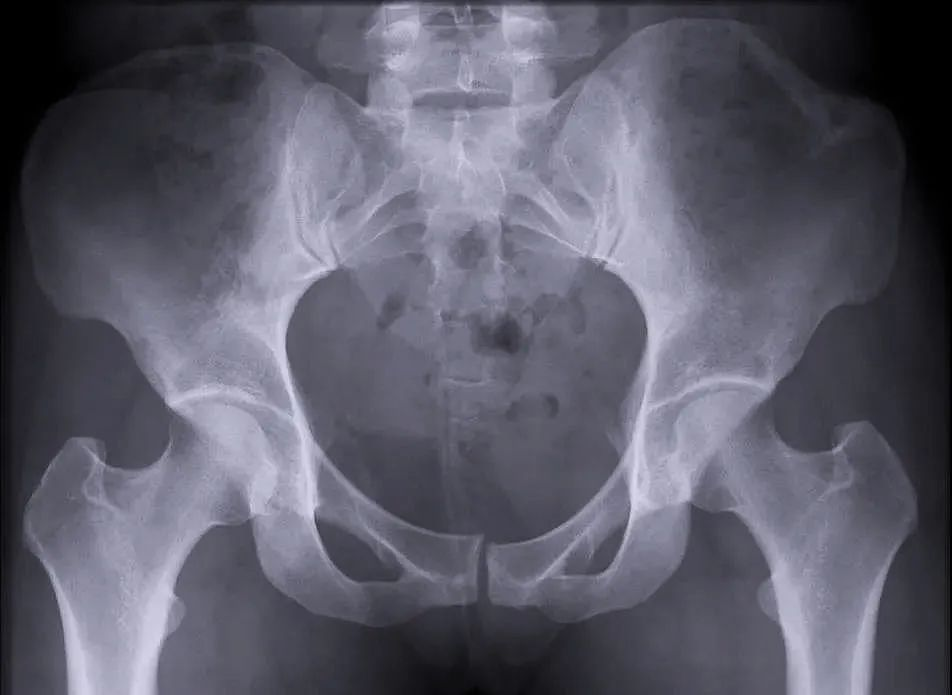

【醫(yī)療科普】:穩(wěn)定性骨折影像

穩(wěn)定性骨折